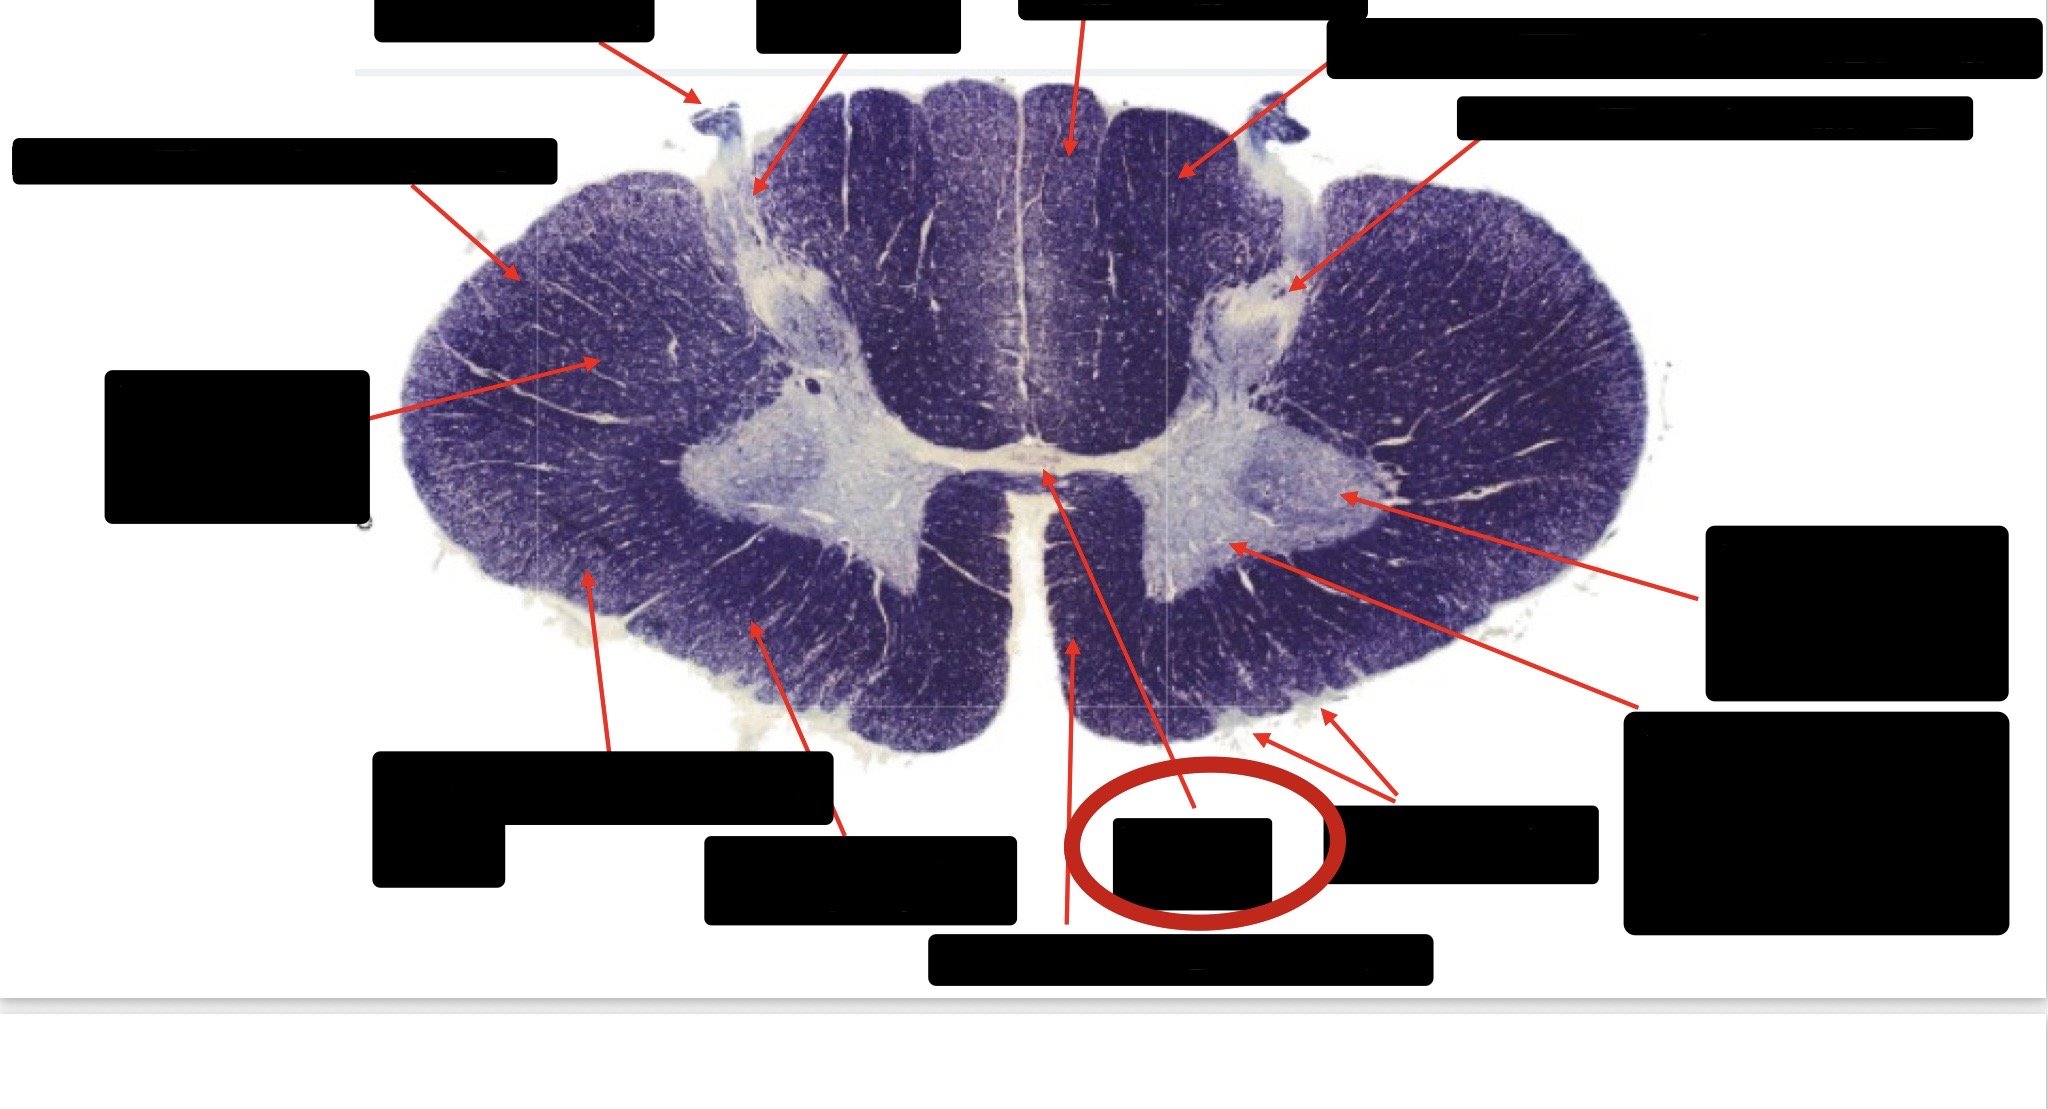

Posterior Column

Large Fiber Entry Zone

Posterior Spinocerebellar Tract

Clarke’s Nucleus

Anterior Spinocerebellar Tract

Ventral Root Fibers

Central Canal

Lissauer’s Tract & Small Fiber Entry Zone

Substantia Gelatinosa

Lateral Corticospinal Tract

Spinothalamic Tract

Anterior Horn Motor Neurons (Distal Muscles)

Anterior Horn Motor Neurons (Proximal Muscles)

Dorsal Rootlet

Lateral Horn

Spinothalmic Tract